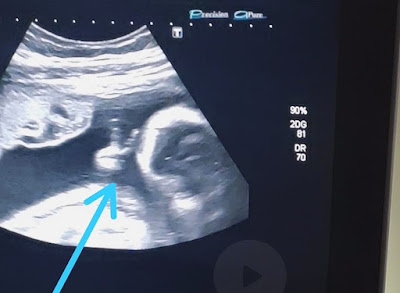

O rapaz conta que ver o ultrassom já é bem emocionante, porque consegue observar como o bebê está e ouvir seu coraçãozinho. Mas, desta vez, ele se deparou com a surpresa de ver o filho Davi fazendo um sinal de ‘V’ com uma das mãozinhas. “Até a médica falou: ‘olha, ele fez o sinalzinho de vitória com a mão’. Eu fiquei sem acreditar”, afirma. Ele encara a situação como um sinal divino de que vai conseguir superar o tratamento e vencer a doença.

“O filho que eu pedi para Deus foi para superar tudo isso que estou passando. Esse sinal foi para fechar com chave de ouro, para eu ter certeza que vou vencer. Se não tivesse ido, não teria visto isso, porque minha mulher não ia conseguir gravar. Aí, eu vou para o ultrassom e tem um sinal desse, parece que é para a minha fé aumentar. Me dá mais força para poder vencer o câncer. Com certeza, foi um sinal divino”, finaliza.